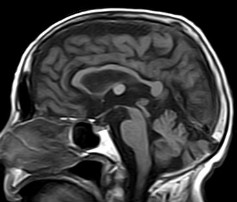

August 2005 - Colloid Cyst

Colloid cysts are benign, epithelial lined lesions, usually located antero-superior to the third ventricle (between the columns of the fornices). They supposedly originate due to an infolding of the neuroepithelium. These cysts may also occur in the choroid plexus of the lateral ventricles, subarachnoid space and brain parenchyma. They comprise approximately 2% of all glial neoplasms. Patients may present with headaches, sudden transient paralysis of both lower extremities, urinary incontinence, personality changes and/or dementia.

• On MRI

• These lesions may be either hypointense or hyperintense on either T1W or T2W images. The variability is due to it's contents. They may contain mucoid material, blood/hemosiderin, macrophages, cholesterol crystals, CSF and various ions (Na, Mg, Ca, Cu, Si, Al, Fe, P).

• Occasionally they may contain serous fluid and follow CSF signal characteristics.

• The lesions are thin walled and peripheral enhancement is common.